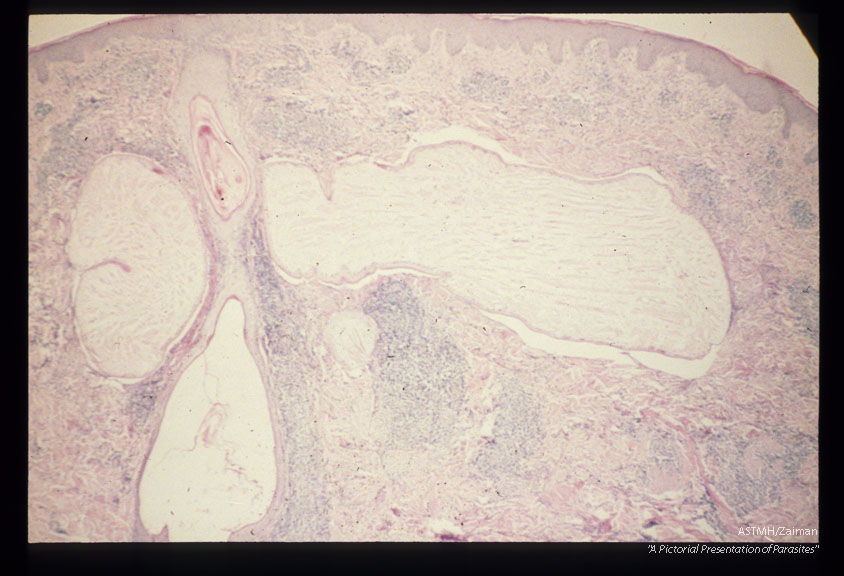

Multiple sections through subcutaneous human tissue containing a sparganum and through the sparganum itself. Note the tremendous inflammatory reaction.

Sparganum

Description: Multiple sections through subcutaneous human tissue containing a sparganum and through the sparganum itself. Note the tremendous inflammatory reaction.